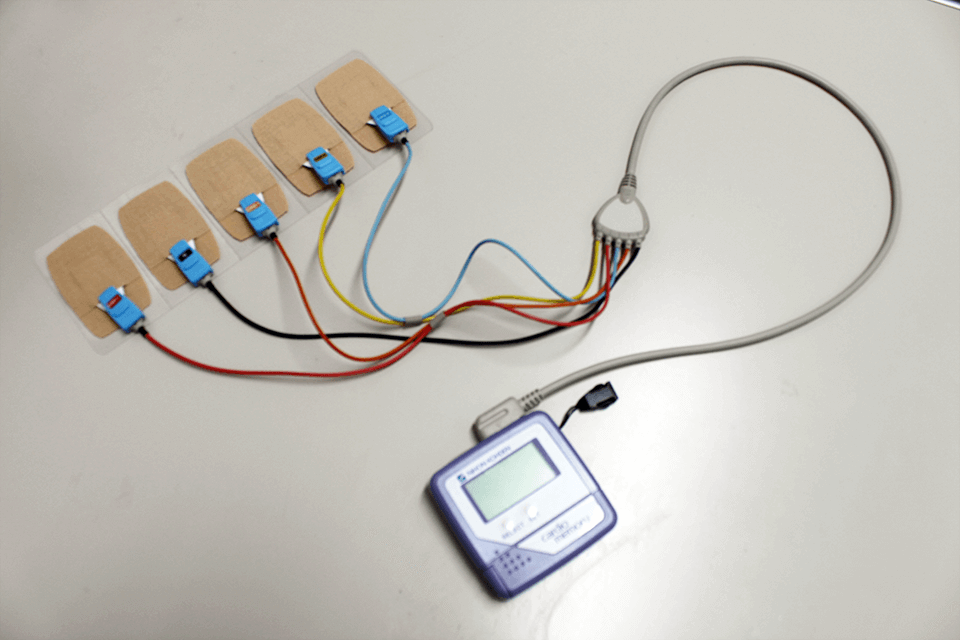

24時間(食事中・運動中・睡眠中なども含む)にわたり、心電図を連続して記録する検査です。

胸にシールの電極を貼り、小型の携帯型心電計を繋ぎます。

不整脈の頻度や種類、発生時間、心拍数の変化などを詳しく調べることができます。

また、日常生活の中でいつ起こるかわからない不整脈や狭心症発作の発見に役立ちます。